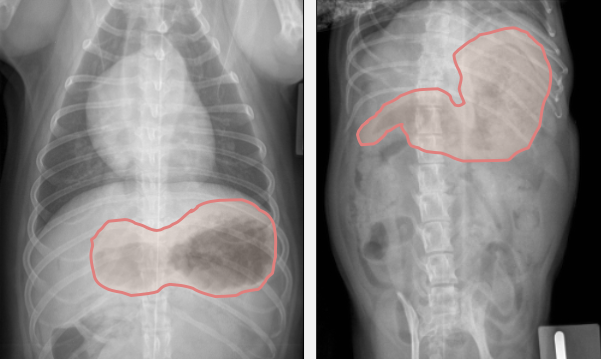

Tracez l’endroit où se trouve l’estomac sur ces radio

Tracez à quel endroit se trouve l’estomac sur ces radio